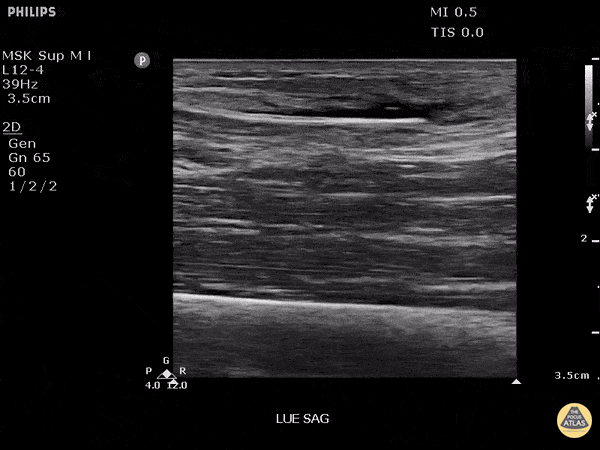

Trauma - Foreign body: bamboo

This patient was seen at a prior facility with pain in arm. X-rays were negative and was sent home with antibiotics. Pain continued to worsen and after ultrasound was employed, a piece of bamboo was discovered. Image courtesy of Robert Jones DO, FACEP @RJonesSonoEM Director, Emergency Ultrasound; MetroHealth Medical Center; Professor, Case Western Reserve Medical School, Cleveland, OH View his original post here